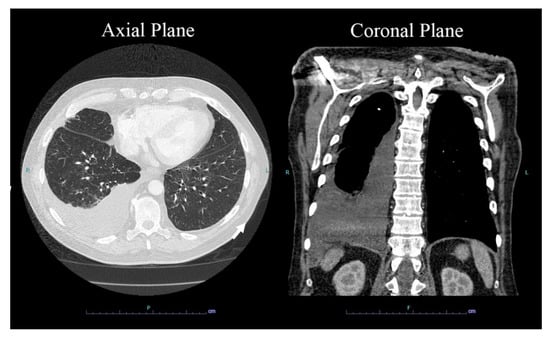

2. Case Presentation